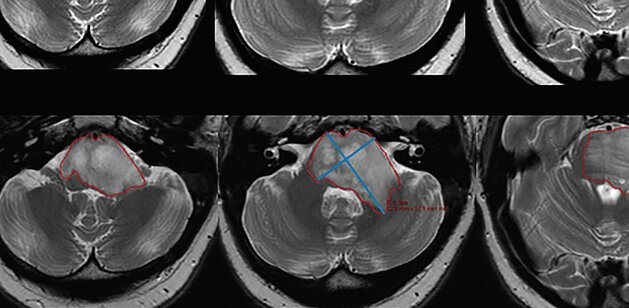

Cincinnati Children's Hospital Medical Center: Study shows variable correlation of change in DIPG tumor size among different measurement strategies

A recent prospective study [1] conducted by researchers at Cincinnati Children’s Hospital Medical Center compared manual 2D, semi-automated 2D, and…